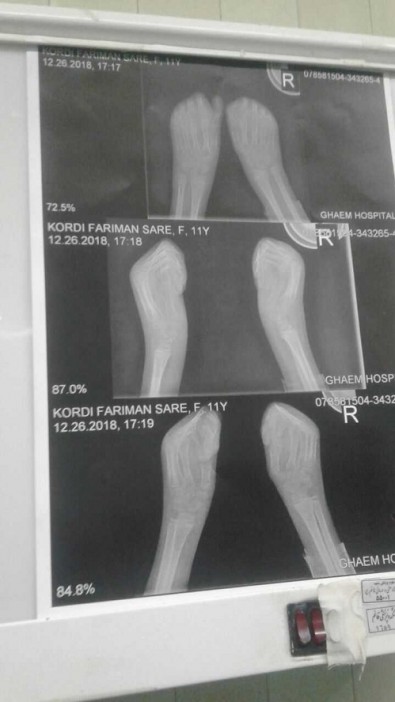

در این روش با استفاده از پرده آمنیون (پرده روی جفت) پوست دست این کودک که از بدو تولد به علت بیماری پروانه ای به حالت(مشت گونه) بود، ترمیم شد.

وی با بیان اینکه انگشتان دست مثل یک پیله به هم چسبیده است و بعد از باز شدن بخاطر نقص پوستی دچار مشکل می شوند، تصریح کرد: پرده های جفت پوشش بسیار خوبی برای دستان بیمار است که در این این بیمار مورد استفاده قرار گرفت.